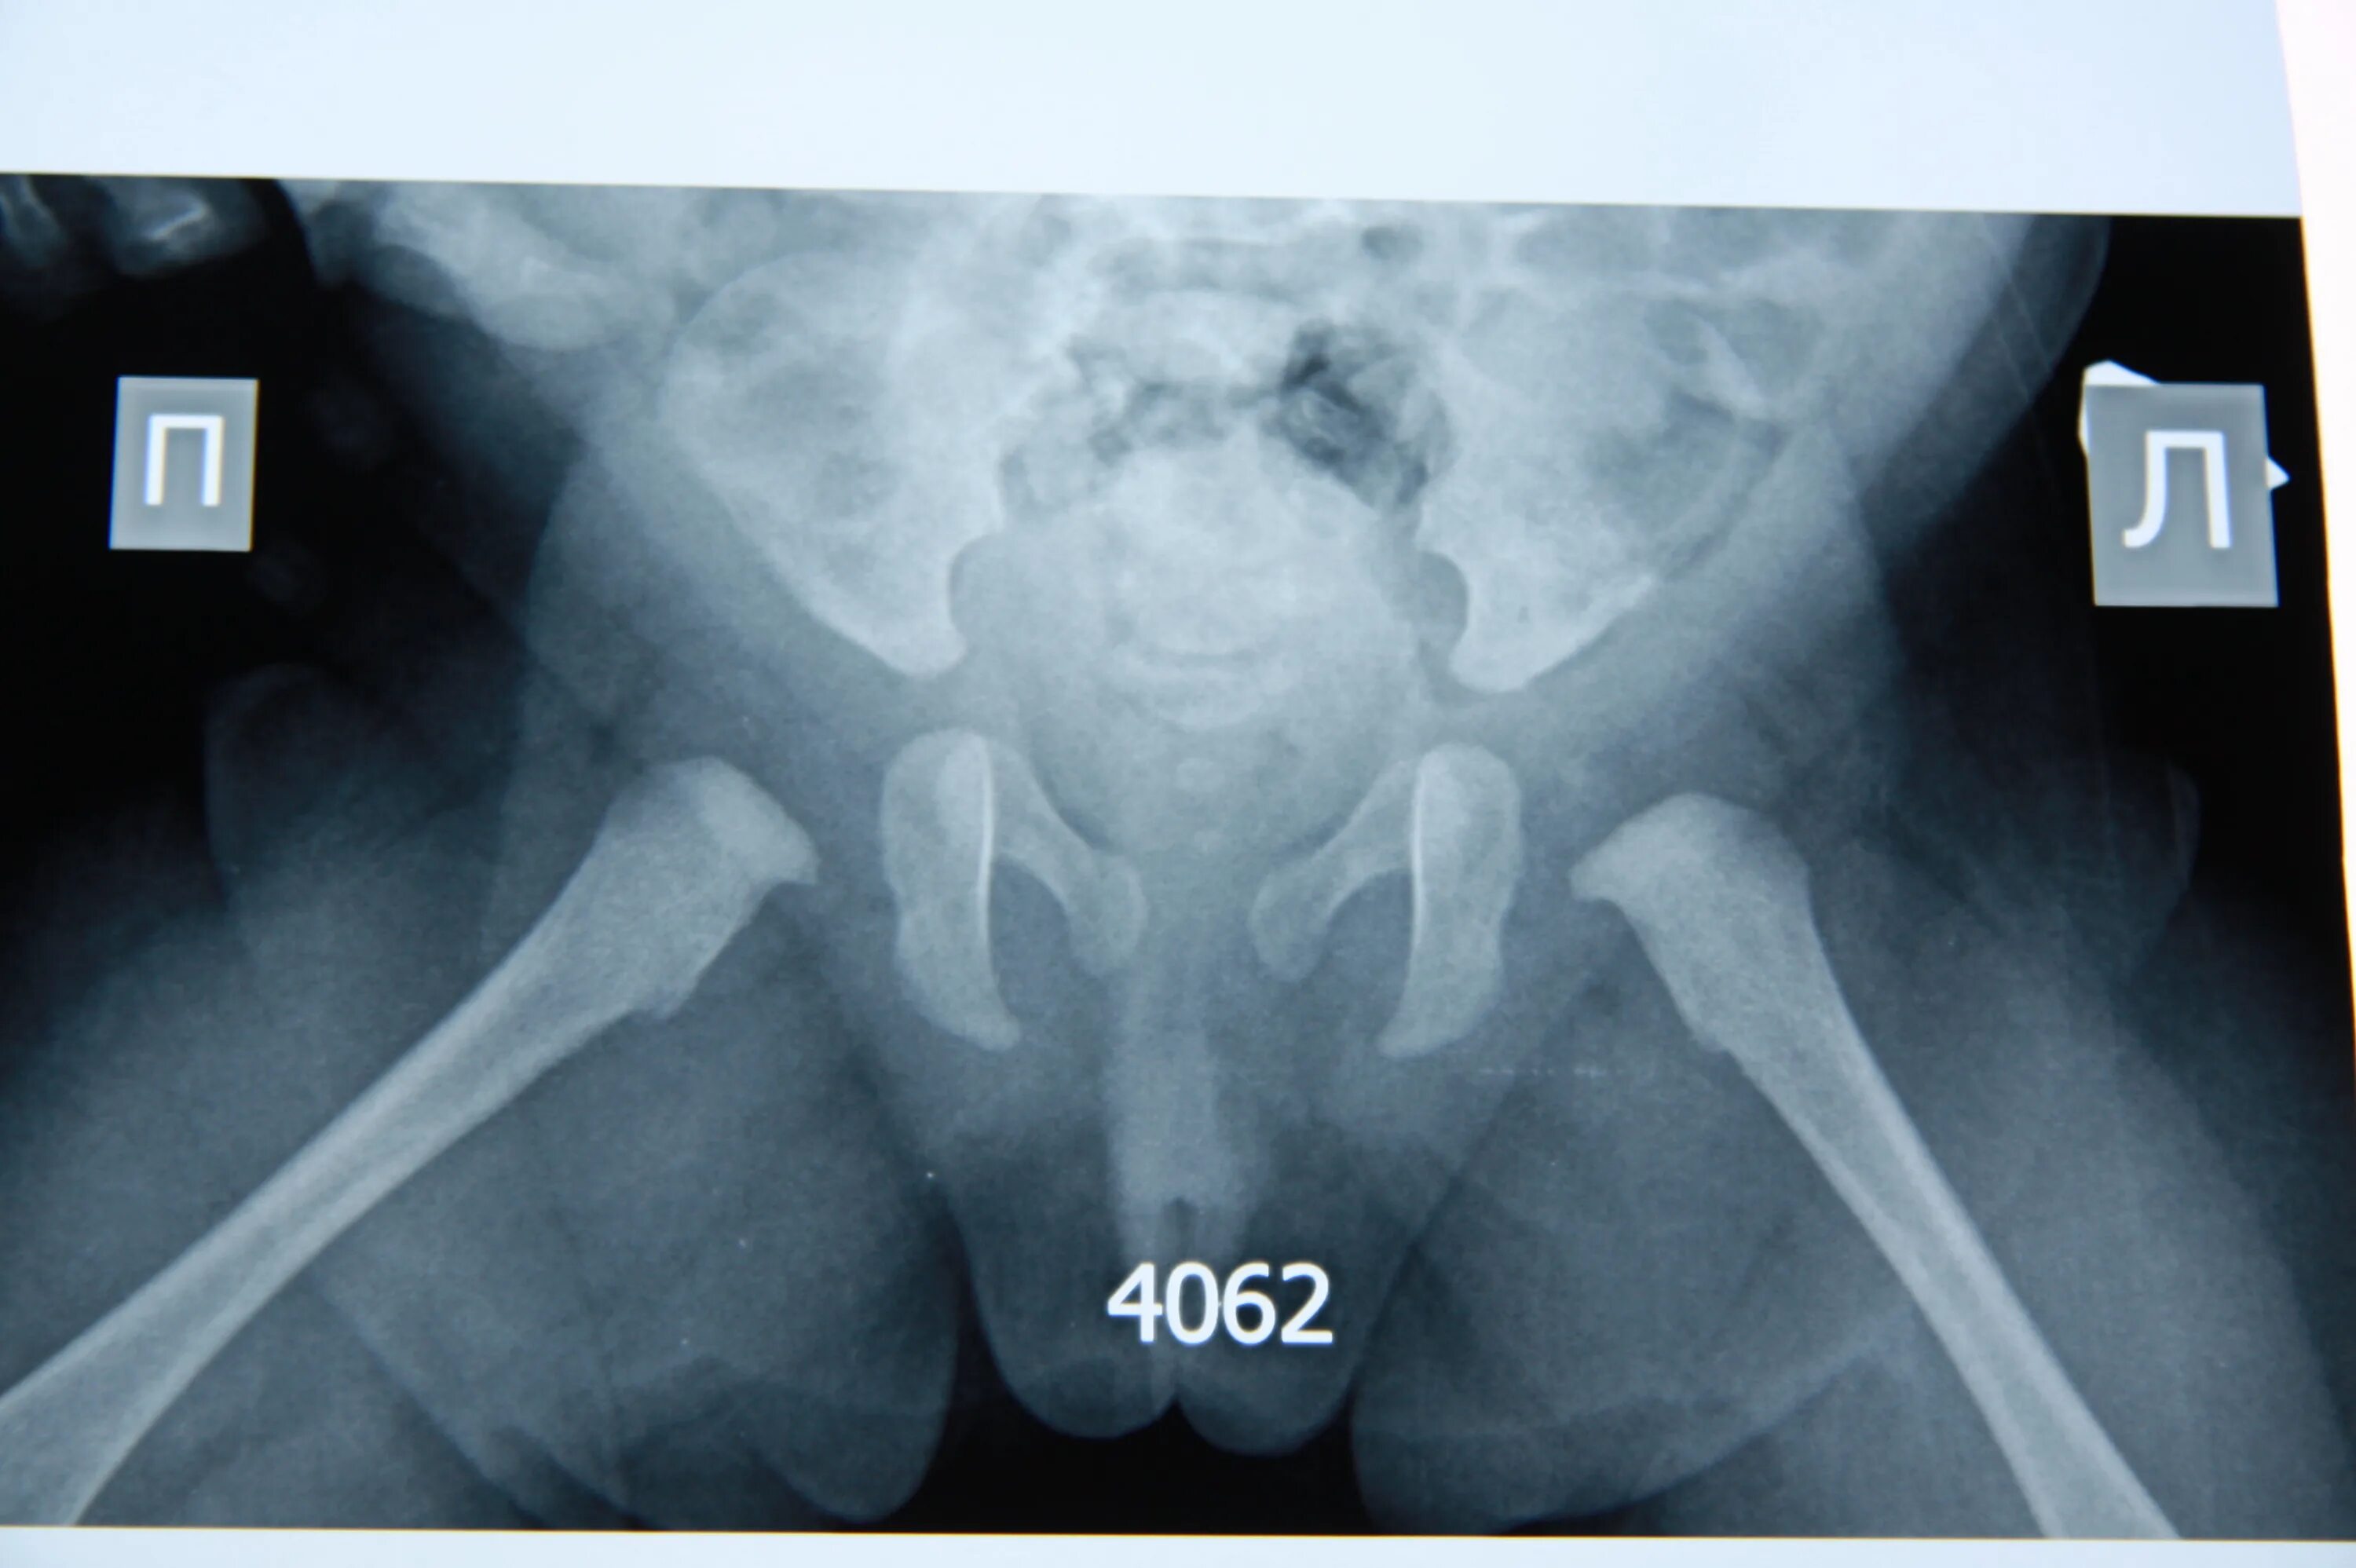

Проекции рентгена тазобедренного сустава